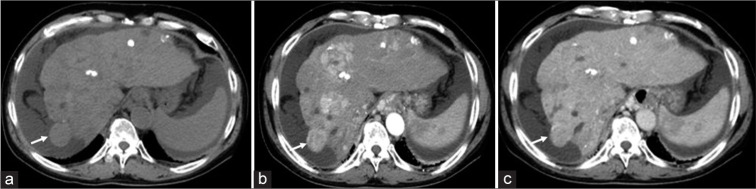

We present a case involving a 60-year-old male with multifocal hepatocellular carcinoma (HCC), emphasizing the critical need for vigilant post-procedural monitoring following the interruption of drug-eluting beads transarterial chemoembolization (DEB-TACE) due to an allergic reaction. The patient, who had a history of various treatments for HCC, underwent DEB-TACE. During the procedure, he experienced an anaphylactic shock, presumably due to an allergy to the treatment components (iodinated contrast agent), resulting in the procedure's discontinuation. Initially stable, the patient was later found to have intra-abdominal bleeding, a complication associated with the vascular lake phenomenon (VLP), detected on post-procedural imaging. Re-embolization using gelatin particles was performed to address the VLP. It remains unclear whether the shock experienced during the DEB-TACE procedure was due to the allergic reaction or the rupture of the VLP. This case underscores the complexities in managing DEB-TACE, the necessity of careful monitoring for VLP, and the challenges in diagnosing and managing allergic reactions during such procedures. In conclusion, it is crucial to consider that VLP can occur at any time during or after DEB-TACE. Assessing the presence of VLP using digital subtraction angiography before the termination of the procedure is essential. However, when an allergy to the iodinated contrast agent is suspected, as in this case, careful follow-up with abdominal ultrasound and computed tomography might be necessary to assess the presence of intra-abdominal hemorrhage associated with VLP.

我们介绍了一例 60 岁男性多灶性肝细胞癌(HCC)患者的病例,强调了因过敏反应而中断药物洗脱珠经动脉化疗栓塞术(DEB-TACE)后进行术后监测的重要性。患者曾接受过多种 HCC 治疗,接受了 DEB-TACE。在手术过程中,他出现了过敏性休克,可能是由于对治疗成分(碘造影剂)过敏,导致手术中止。患者最初病情稳定,但后来发现腹腔内出血,这是一种与血管湖现象(VLP)有关的并发症,在手术后的成像中被发现。为解决 VLP 问题,使用明胶颗粒进行了再次栓塞。目前还不清楚 DEB-TACE 过程中出现的休克是由于过敏反应还是 VLP 破裂所致。该病例突出说明了 DEB-TACE 管理的复杂性、仔细监测 VLP 的必要性以及在此类手术中诊断和管理过敏反应的挑战性。总之,必须考虑到在 DEB-TACE 期间或之后的任何时候都可能出现 VLP。在手术终止前使用数字减影血管造影术评估是否存在 VLP 至关重要。不过,如果怀疑患者对碘化造影剂过敏,就像本病例一样,可能需要通过腹部超声波和计算机断层扫描进行仔细随访,以评估是否存在与 VLP 相关的腹腔内出血。